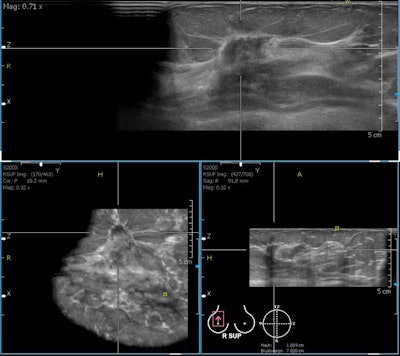

This technology is based on computer generation of a 3D imaging dataset obtained from many parallel 2D images. It offers a different approach with a variety of benefits, he said. Images are obtained by the sonographer in a standardized fashion; whole breast datasets can be reviewed at any time after the examination, which reduces operator dependence, and image fusion with MRI, for instance, is possible.

However, handheld ultrasound is a highly operator- and experience-dependent modality. Real-time adjustments (gain, focal zones, dynamic range, pressure, etc.) are necessary for good results, and abnormalities have to be recognized at examination, otherwise they are missed. With automated breast ultrasound, on the other hand, there are standardized views (like in mammography) for better reproducibility. Acquisition is separated from interpretation, and second reading, like with screening mammography, is an option, he continued.

Limitations include lower ultrasound frequency than for handheld devices, no Doppler analysis or elastography imaging, difficulty in scanning the axillary region, and the relatively large amount of data (0.7-1.0 GB per examination). Artifacts can be an issue due to the bigger transducer (15 cm).